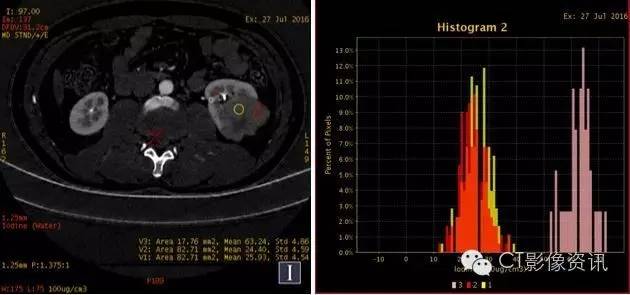

CT值单位:Hu 增强能谱扫描各期碘基物质图观察

左肾病灶(红色ROI 2)基物质碘含量与左肾髓质(黄色ROI 1 )相似,与左肾皮质(粉色ROI 3)存在较大差异。 右肾病灶基物质碘含量与右肾皮质、髓质纯在较大差异。且左、右肾病灶基物质碘含量明显不同。(见表二)

左、右肾病灶及肾实质基物质碘含量明显不同,其基物质碘含量亦不相同。(见表二)

表二:增强能谱扫描双肾及肾实质各期碘基物质测量结果

碘基物质测量(单位:100ug/立方厘米)